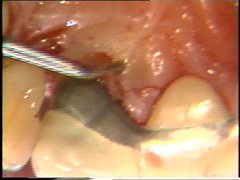

Visión palatina:

Eliminación del tejido de granulación.

El colgajo

se levanta teniendo cuidado de no desgarrarlo.